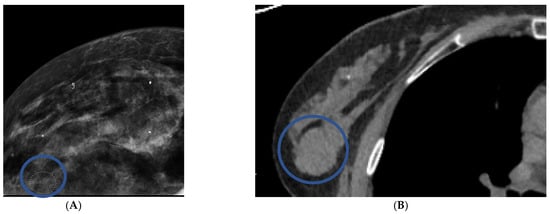

Forty-nine patients had masses on mammograms, of which 16% were cancer, and there were forty-four masses identified on CT, of which 20% were cancer. On chest CT, the average size of a cancerous mass was larger; no nodules less than 10 mm were cancer (p = 0.06) (Table 4) (Figure 2). The average HU of cancerous nodules was higher; no cancer had a HU of less than twenty-four (p = 0.003). Cancerous nodules were often lobular or spiculated (Figure 3). All nine cancerous nodules on CT were recommended for biopsy and two of thirty-five benign nodules were recommended for biopsy.

Figure 3. Distinguishing features of benign versus malignant masses on contrast-enhanced chest CT scans in axial projection. Patient (A) has a benign nodule with smooth borders and HUs of less than twenty. Patient (B) has a malignant nodule with lobular borders and HUs greater than twenty.